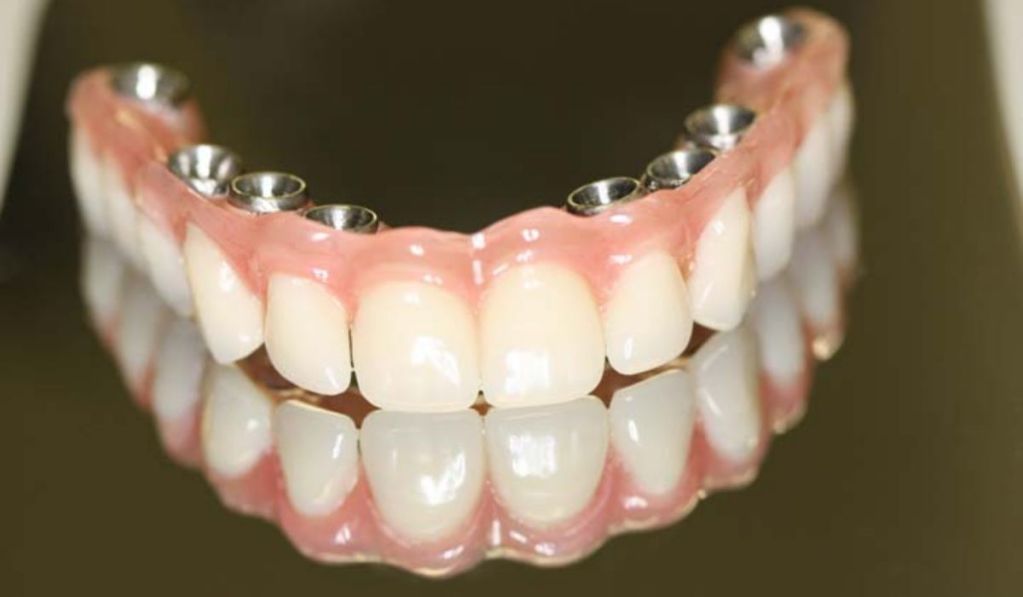

Após o período de osseointegração, geralmente entre três e seis meses, a prótese definitiva é confeccionada.

Nessa fase, são considerados aspectos estéticos, fonéticos, oclusais e biomecânicos, com escolha criteriosa dos materiais e desenho protético adequado.

O Protocolo All-on-4 é uma técnica de reabilitação oral fixa que utiliza quatro implantes dentários estrategicamente posicionados para suportar uma prótese total fixa em pacientes totalmente edêntulos ou com indicação de exodontia total.